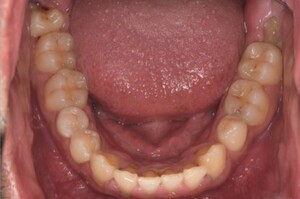

症例3

来院2回目、TBI後

症例

SRP後

初診時、TBI前

基本情報

年齢・性別 27歳・男性

主訴 主訴:左右下の歯ぐきに違和感がある

治療部位:全顎

治療内容 1.歯周基本検査、レントゲン撮影、口腔内写真、歯磨き指導、歯石除去、着色除去

2.SRP(スケーリングルートプレーニング)、再評価

その他

3.親知らずの抜歯

4.カリエス処置:右上1.2.3左上1.2.3右下6左下7CR(レジン充填)、右下7セラミックIn

5.定期検診

治療期間 6ヶ月

治療費 ※歯周基本治療の費用:PMTC以外保険診療3割負担

合計:19,680円

1.初診検査(歯周ポケット検査.レントゲン撮影):3,010円

2.歯磨き指導、歯面の歯石除去:1,410円

3.PMTC(自由診療):5,500円

4.SRP(歯周ポケット内の歯石除去)×4回:約2,000円/回

5.再評価:1,760円

(2023年12月現在)

リスク・副作用 ・最初は歯磨きをすると歯ぐきから出血するが毎日ホームケアを続けることで出血が徐々になくなる

・歯ぐきが腫れている状態が改善されると歯ぐきが引き締まり退縮するため、歯ぐきが下がったように感じることがある

・歯ぐきが引き締まると歯間が開いたように感じることがある

・歯ぐきが引き締まると知覚過敏の症状がでる可能性がある

・一度歯石を除去しても毎日のホームケアを怠ると再度歯石がつく

・治療後も再発を防ぐために定期的なメインテナンスが必要である

治療方針 1.初診検査(レントゲン撮影、口腔内写真、歯周検査、歯磨き指導)

2.歯磨きチェック、歯石除去、PMTC

3.SRP

4.再評価

特記事項 ・歯科医院は今回初めて

・タバコは24歳まで3年ほど吸っていたが健康のためにやめた

・親知らずは右下以外抜歯

・歯ブラシはルシェロP20M、補助用具はフロスを処方

担当者所見 全体的に歯と歯ぐきの境目に歯垢(細菌の塊)が残り、日々のホームケアで落とし切れていなかったことと、歯科医院への定期検診の習慣がなかったことから、全顎的な歯肉炎になってしまったと考えられる。

歯周基本治療とホームケアで歯ぐきの腫れや歯周ポケット、出血率などかなり改善されたが、出血がまだ0%ではない為、引き続き歯ブラシの当て方をお伝えしつつ今後は定期検診で3ヶ月おきに再発しないよう一緒に管理していく。